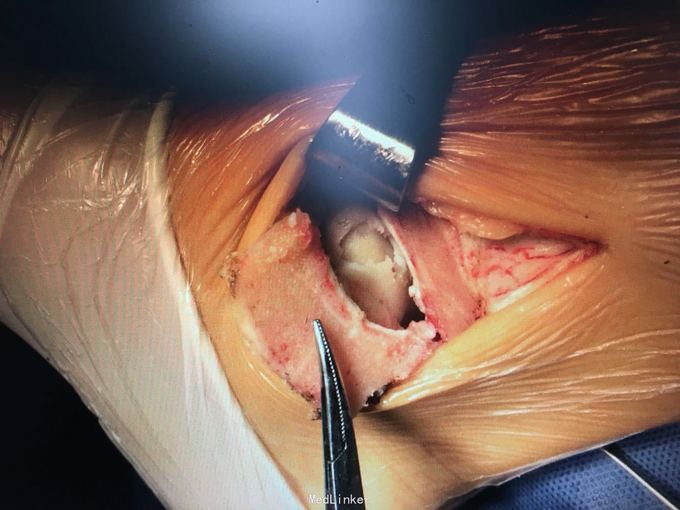

诊断和手术方式如题 直接上图

术后第二天进行非负重下踝泵练习,2周内限制踝关节外翻和外旋,6-8周后根据骨愈合情况下地负重 目前有北京积水潭报道全关节镜下完成此手术,我们将进一步探索,另外,股骨外侧髁非负重区取骨后膝关节痛的情况可见,取骨区域尚需改进